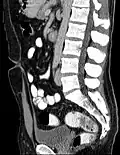

• Urachal cyst: there is no longer a connection between the bladder and the umbilicus, however a fluid filled cavity with uroepithelium lining persists between these two structures.

The urachus is also subject to neoplasia. Urachal adenocarcinoma is histologically similar to adenocarcinoma of the bowel. Rarely, urachus carcinomas can metastasise to other regions of the body, including pelvic bones and the lung.[7]